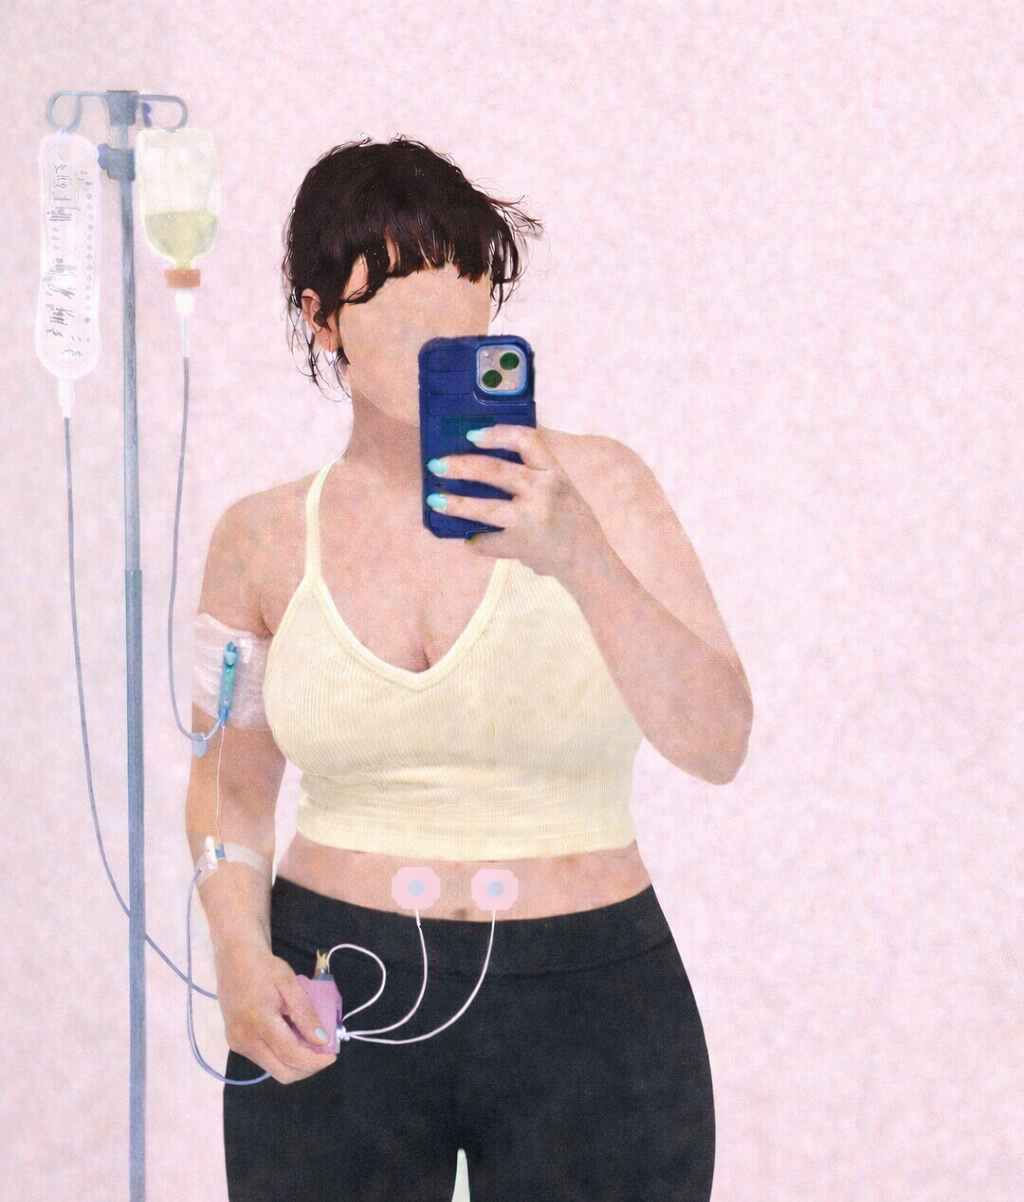

Endometriosis isn’t “just bad cramps.” It’s chronic, often misunderstood diseases that affects 200 million women. Yet, it still dismisses, underdiagnosed, and under-treated.

If you click the links below, you will find trusted resources, education, and advocacy tools to help you understand endo, support them living with it, or feel less alone if this is your reality too.

Pain deserves to be believed. Care should never be optional.